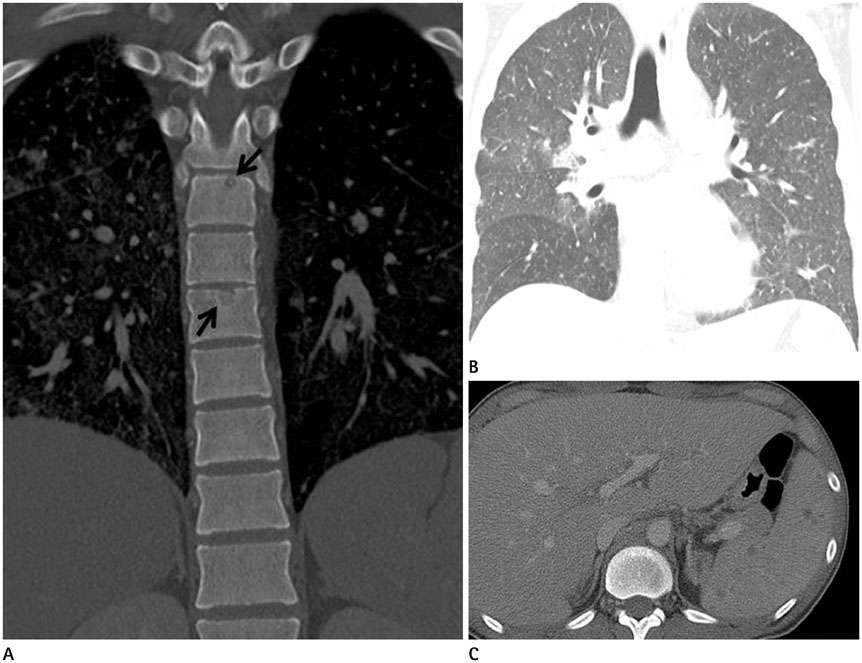

- The spine is the most common site of skeletal involvement in tuberculosis. The radiologic features are reportedly characterized by destruction of the vertebral body, subligamentous extension or subchondral penetration, frequent paravertebral abscess formation and late involvement of the disk space. We experienced a case of a 25-year-old male who was a human immunodeficiency virus carrier without antiretroviral therapy. Incidental findings on abdominal computed tomography included multiple well-demarcated and ovoid osteolytic lesions with hyperdense rims disseminated in the thoracic, lumbar, and sacrum vertebrae, as well as in both ilii. On the lumbar spine magnetic resonance imaging, multiple small round lesions of isointense signal intensity with peripheral hyperintense rims were found on both T1- and T2-weighted imaging. The lesions had peripheral rim enhancement on gadolinium-enhanced T1-weighted imaging. Based on our experience, this rare image finding is one of the manifestations of disseminated tuberculosis.